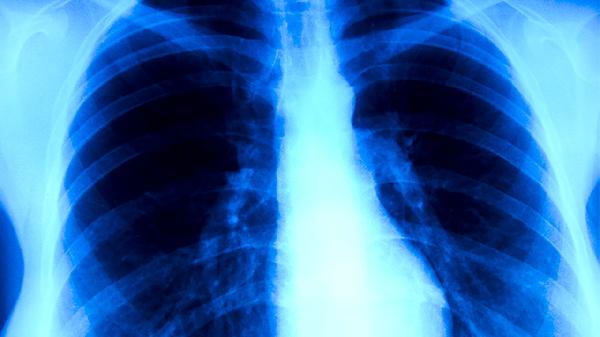

治疗期间应保持居室通风干燥,每日紫外线消毒30分钟。饮食需做到荤素搭配,适量增加山药、百合等润肺食材。康复期可进行八段锦等柔缓运动,避免剧烈活动诱发咯血。严格实施呼吸道隔离措施,密切接触者需接受预防性筛查。建议每2个月复查胸部CT,治疗结束后仍需随访2年监测复发情况。